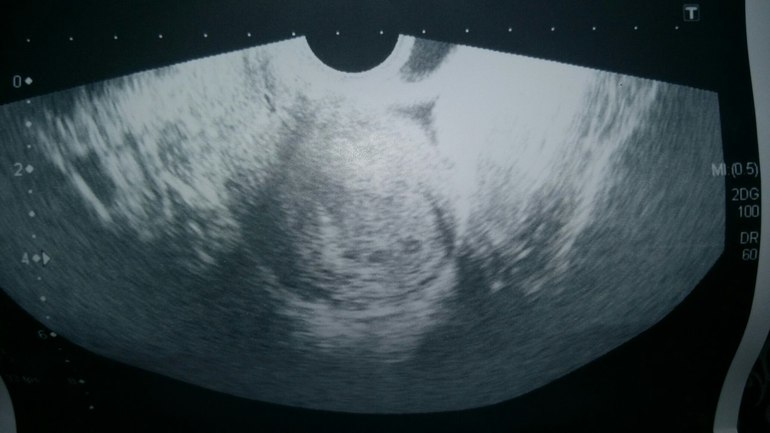

Девочки, что вы видите? это двойня или нет?

Были на узи. Поставили нам под вопросом двойню. Срок 3 недельки.Но врач сказала, что она не уверена. и добавила-тут либо двойня, либо угроза. Посмотрите, пожалуйста. Может у вас остались снимки с вашего узи, было бы интересно очень посмотреть. и любому мнению буду рада. Вот фото с узи

Тоже вижу три кружочка на втором снимке. У меня в 6-7 недель тоже были две точечки маленьких. А желточный мешок видно было на УЗИ, на снимке рано еще

Вижу даже три кружочка, два явно видно, и точечки внутри, третий мутный такой. В 7-8 нед будет понятно.

спасибо за ответ!)) третий на снимке видимо так получился. на экране вот было отчетливо 2 кружочка. но сказала, что это может быть и просто угроза... вот теперь бы дожить до следующего узи...))))

У меня в 3-4 недели было видно только одно плодное яйцо. В 7-8 уже было два. Но всякое бывает. Похоже, что у вас двойня...